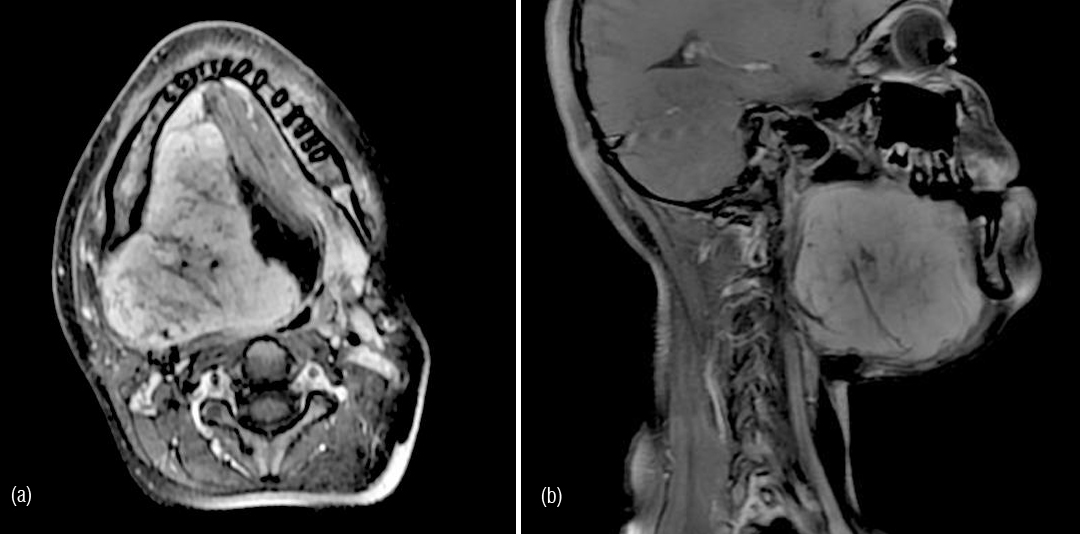

13-year-old girl presented with 2 months history of firm, non-tender swelling in right upper neck just beneath the mandible. Mild deviation of tongue was noted by parents since the age of 2 years for which no medical advice was sought. There was no history of recent trauma. Family history was non-contributory. There was no history of pain or other associated sensory symptoms. On physical examination, mass was felt in submandibular and sublingual area which was firm and immobile. There was no restriction of mouth opening, overlying skin and intraoral mucosa was normal. MRI neck was done which revealed ill-defined hypo intense mass with areas of intensity, approximately 5 x 5.2 x 5.3 cm in size, in right sublingual, submandibular region extending to parapharyngeal space cranially upto base of skull with widening of foramen lacerum and medial aspect of greater wing of sphenoid. Lesion was found causing mass effect over posterior tongue and oropharynx. Lesion did not show enhancement after contrast administration.

Patient again presented with increase in the size of swelling and slurring of speech 6 months later in Dec 2013. Clinically right submandibular area swelling with deviation of tongue was noted. MRI neck revealed progression of the recurrent lesion with size approximately 7.9 x 6.4 x 8 cm.

Figure 1a,b: MRI axial and saggital - lesion in right sublingual and submandibular region.